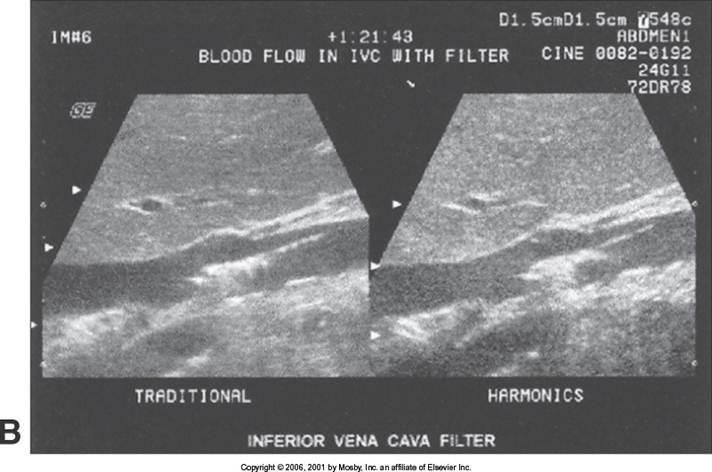

IVC Filters